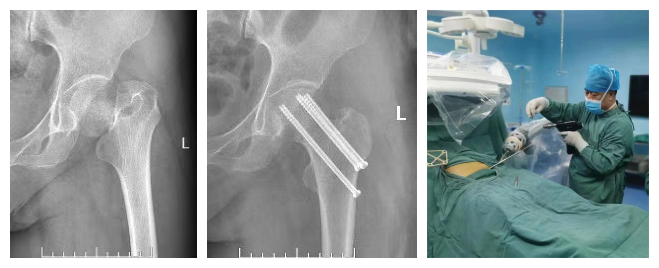

机器人辅助下股骨颈骨折闭合复位内固定手术